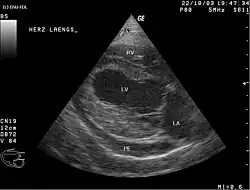

Bei großen Perikardergüssen sitzen die Patienten aufrecht, sind sehr ängstlich, haben starke Atemnot und gestaute Halsvenen, es besteht meist eine Zyanose; der Puls ist klein und weich. Durch Abklopfen des Brustkorbs kann nur ein sehr großer Erguss festgestellt werden.[3] Die einfachste und schnellste Methode, um einen Erguss zu erkennen, ist der Ultraschall. Auch im CT kann man einen Perikarderguss gut sehen. Die Flüssigkeit des Perikardergusses kann man zytologisch auf maligne Zellen und auf Bakterien untersuchen. Die Punktion des Herzbeutels ist technisch nicht einfach. Je größer der Erguss ist, desto einfacher und zugleich wichtiger ist die Punktion.